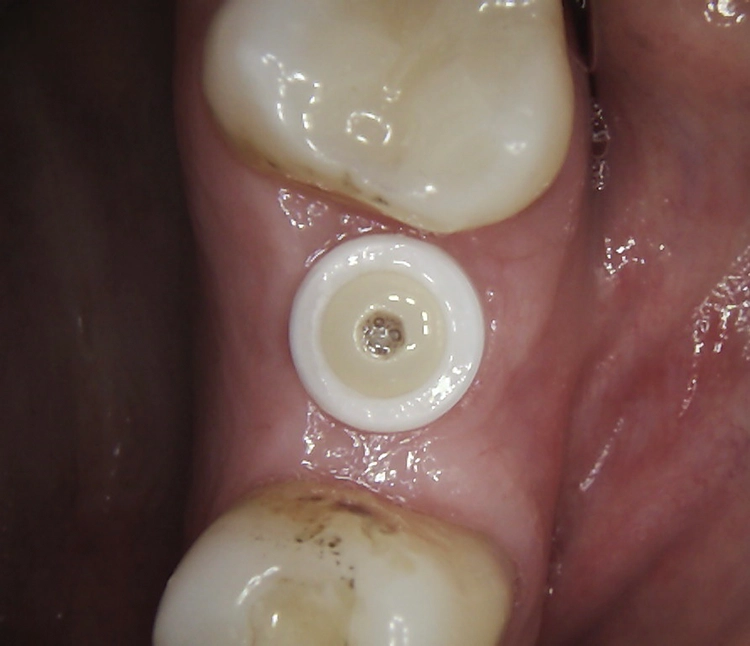

Abb. 2: Repräsentativer Fall von ABH Grad B Septus Typ II. a) Ansichten vor der Installation. Röntgenaufnahme der periapikalen Läsion an einem wurzelkanalbehandelten Molaren und klinische Ansicht der Typ-II-Socket nach der Extraktion. b) Die Ansichten nach der Installation zeigen das Implantat innerhalb des interradikulären Septums und das über dem Implantat platzierte A-PRF. c) Nachuntersuchungen nach 10 Tagen bzw. 2,1 Monaten. Die Röntgenaufnahme zeigt die Knochenbildung zwischen der Sinusmembran und dem apikalen Teil des Implantats. d) Jüngste Nachuntersuchung nach Einsetzen der Prothese.

Abb. 3: Repräsentativer Fall von Grad A Typ I. a) Präoperative Ansicht. Röntgenbild der periapikalen Läsion an einem wurzelkanalbehandelten Molaren. Die Höhe des Alveolarknochens zeigt Grad A an. b) Klinische und radiographische Ansicht der Implantatinsertion unter Verwendung einer Einheilscheibe mit großem Durchmesser (6×8 mm). A-PRF wurde um das Implantat und unter der Scheibe platziert. c) Nachuntersuchung nach 5,9 Monaten vor und nach der Zementierung und Aufbereitung. d) Jüngste Nachuntersuchung nach Einsetzen der Prothese

Die SDS-Zirkoniumdioxidimplantate wurden mit zementierten Pfosten weiter aufbereitet (Abb. 1d, 3 und 4c) und nach 4,74 + 0,95 Monaten Einheilzeit mit endgültigen Kronen versorgt. Die Balkonform ermöglichte ein natürliches Emergenzprofil, das die definitiven Kronen wie die Standardform ausrichtete sowie die Gesundheit des Weichgewebes und die Osseointegration förderte. Bei jeder Nachuntersuchung wurden Stabilität des Implantats, Zustand des umgebenden Gewebes und Vorhandensein von Zahnstein beurteilt.